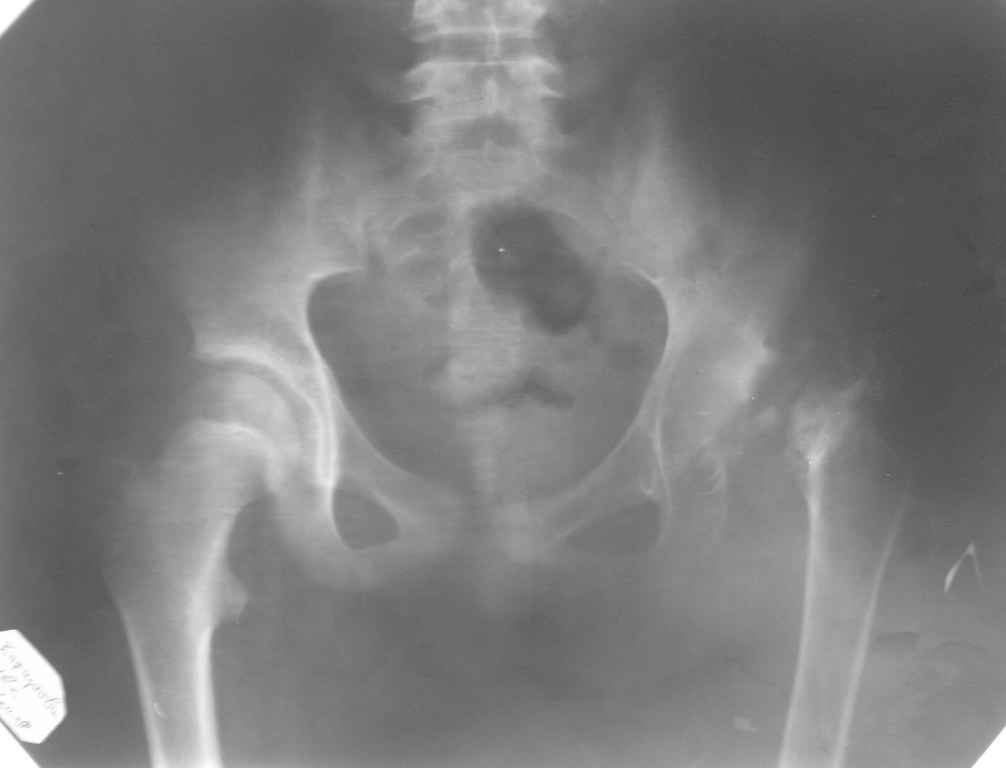

Снимок во вложении по поводу АНГБ

Уважаемый Гуфрон,

А почему Вы спрашиваете о тактике только ОПЕРАТИВНОГО лечения?

Может быть, есть смысл обсудить тактику ВЕДЕНИЯ девочки 12 лет с травматическим некрозом головки бедра?

Глубокоуважаемый Виталий Евгеньевич! Был бы рад если можно как то консервативно вести эту больную хотя бы до 25-30 лет. Уже 2 года как она не наступает на эту ногу, ходит естественно с костылями, мы считаем, что не за горами остеопороз. Попытаюсь отправить снимок мальчика 5 лет с паралитическим вывыхом которому мы произвели операцию Эпископо - это всё на что мы способны. Если будут предложения заранее благодарен. Спасибо!

Уважаемый Гуфрон! В этом возрасте и при подобной деформации не следует опасаться реконструктивных вмешательств на суставе. Один из вариантов: низведение большого вертела и коррекция свода вертлужной впадины, возможно потребуется и артротомия для лучшей центрации головки бедра. АИФ